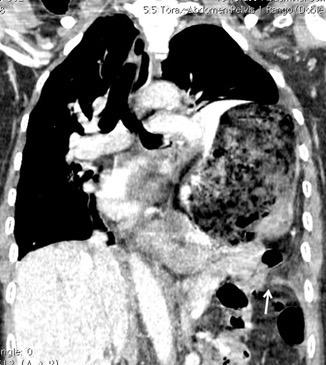

T. mixto de células germinales del testículo

izquierdo Metástasis pulmonares. (flechas verdes). Ganglios paratraqueales. (flechas amarillas). Ganglios retroperitoneales (flechas negras)

Tawfik A et al. Trans-diaphragmatic Pathologies: Anatomical Background and Spread of Disease on cross-sectional Imaging. Current Problems in Diagnostic Radiology. 2021.